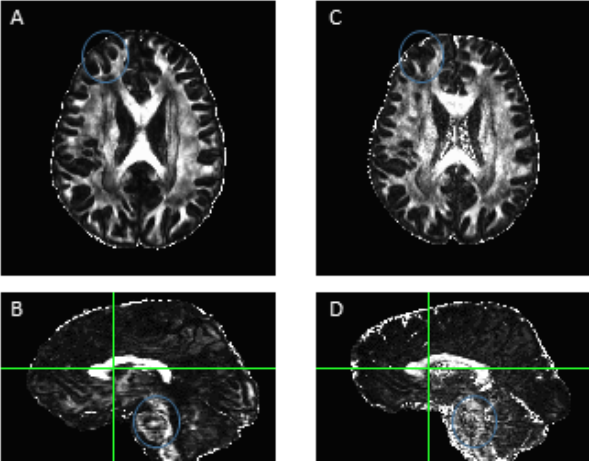

Diffusion image processing and analysis. We developed our own advanced diffusion processing pipeline (ADPP) that follows similar steps to the diffusion pipeline data in the FSL software package (FMRIB, Oxford University) but allows greater spatial mapping in order to maintain the resolution of the acquired data. Image processing methods were implemented primarily using AFNI and Camino (http://afni.nimh.nih.gov/afni), (http://camino.cs.ucl.ac.uk). Processing consists of multiple steps that obtained orientation dispersion metrics for grey matter and “free-water” estimates of the fractional anisotropy (FA) in both grey and white matter. ROIs (e.g., regions within spoken naming, orthographic, and sentence processing networks) are used to extract the DTI indices of white matter integrity and then each ROI is masked to include only white matter. The resultant, ROI-specific DTI metrics, are then stored in the database and compared between time points. Whole brain analyses are also conducted due to the higher quality of our diffusion data and Figure 2: Example of the hypo- (blue) and normal (yellow) perfused regions in two different stroke participants. The lesion mask generated by our automatic segmentation algorithm is shown in red. An additional left hemisphere mask is used to limit analysis of the hypo-perfused tissue. Figure 3: ADPP results in A and B, FSL output results in C and D. We have developed a pipeline that calculates the Neurite Orientation Dispersion and Density Imaging (NODDI) metrics, which provides an estimate of the FA without the contamination of “free water” in each voxel. Using our improved diffusion pipeline, the FA maps are much sharper and allow for better detection of the skeleton. Probabilistic DTI fiber tracking is also conducted using the probabilistic diffusion tractography software, which accounts for crossing fibers. The ROIs masked for white matter will serve as seed and waypoints to examine language network pathways.